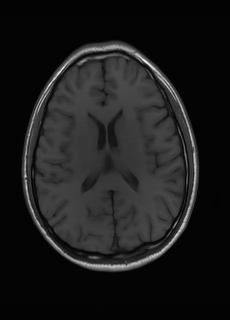

As we observe from the right image in Fig. 2, our BRM, both from MIMO and SISO settings, predicts the performance of dedicated models with a high correlation. We further choose the best three , and perform the last stage of fine-tuning accordingly to (6). A visual evaluation on real data is shown in Fig. 3. For simulated data, please refer to the Supplemental Material section.

Base on the best performing , we perceive that among , , and FLAIR, the results are best when is sampled the most. We suggest that this makes intuitive sense as images provide the best contrast out of the three sequences, which can compensate for the details lost in other images. The same observation can be made on the simulated data, where both and FLAIR show good contrast. When the time setting is changed to non-uniformity, we can see that our search for the best sampling strategy reflects the change. is sampled more as a result of faster acquisition time, while is still sufficiently sampled.

| Sequence | LR | SISO | MIMO | MIMO tuned | GT |

|---|---|---|---|---|---|

(a) 34.38/0.9371

(a) 34.38/0.9371

|

(b) 42.42/0.9883

(b) 42.42/0.9883

|

(c) 44.60/0.9920

(c) 44.60/0.9920

|

(d) 45.50/0.9940

(d) 45.50/0.9940

|

(e) PSNR/SSIM

(e) PSNR/SSIM

|

|

(f) 29.74/0.8903

(f) 29.74/0.8903

|

(g) 36.25/0.9734

(g) 36.25/0.9734

|

(h) 36.42/0.9752

(h) 36.42/0.9752

|

(i) 37.70/0.9832

(i) 37.70/0.9832

|

(j) PSNR/SSIM

(j) PSNR/SSIM

|

|

(k) 39.89/0.9311

(k) 39.89/0.9311

|

(l) 43.94/0.9864

(l) 43.94/0.9864

|

(m) 44.74/0.9883

(m) 44.74/0.9883

|

(n) 45.49/0.9894

(n) 45.49/0.9894

|

(o) PSNR/SSIM

(o) PSNR/SSIM

|